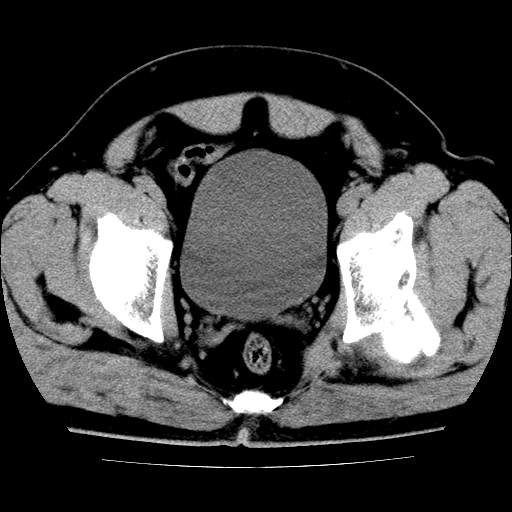

男,42岁,车祸伤后左髋关节疼痛剧烈1小时。

左髋关节脱位并髋臼骨折,左髋关节积血。

左髋关节后脱位并髋臼骨折,左髋关节积血

左髋关节后脱位,大小转子皮质撕脱骨折,关节腔“脂血症”,左侧盆底少量积血,左侧髋臼邻关节囊肿。

左髋关节后脱位并髋臼骨折、股骨头前方骨折,左髋关节积血 。

左髋关节(股骨头)后脱位,并髋臼及股骨头骨折,左髋关节积血。

左髋关节后脱位并髋臼后缘骨折、股骨头前方骨折,左髋关节积血 。我遇到过一例。